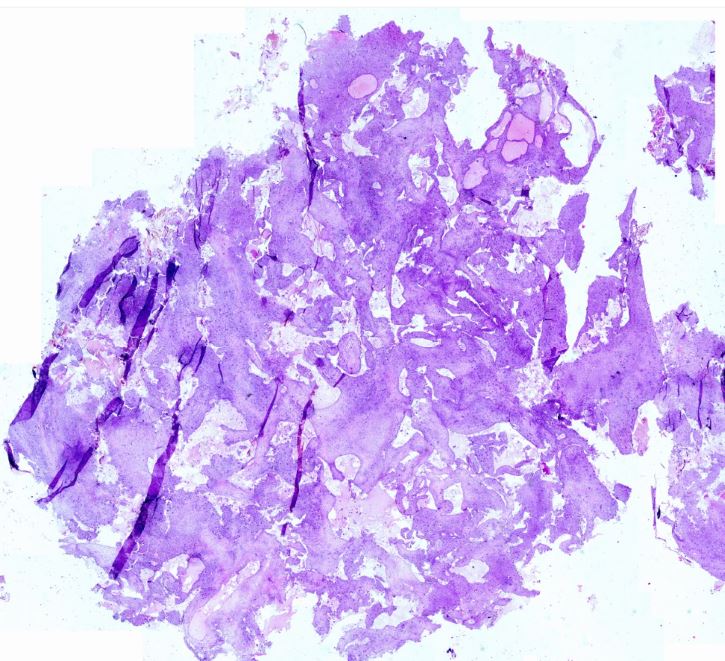

Anevrizmal kemik kisti